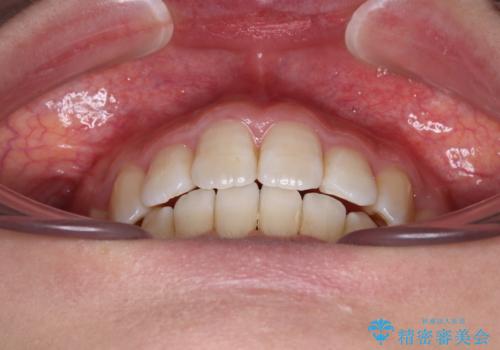

デコボコと出っ歯 抜歯矯正でスッキリとした口元に

デコボコの解消で歯が磨きやすくなり、抜歯矯正により口元の突出感が大幅に改善され、スッキリした口元になりました。